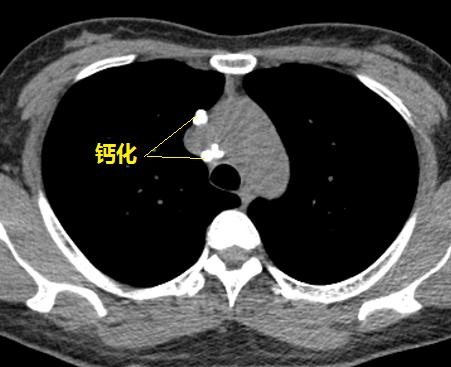

图1~图7 胸部CT示双肺多发钙化

问题在哪儿?

肺部钙化灶脱落,掉进左主支气管(图8),因为钙化病灶是坚硬的、锐利的,就像一个石头在不断地刺激支气管粘膜,导致患者咳嗽。

图8 胸部CT